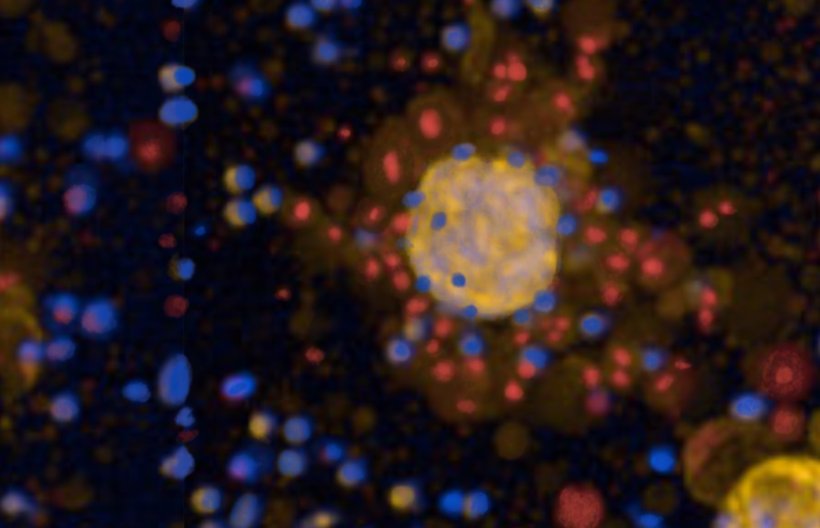

© BIH | Michael Schmück-Henneresse, grafisch bearbeitet

Forscher des BIH Center for Regenerative Therapies des Berlin Institute of Health in der Charité (BIH) haben jetzt ein Verfahren entwickelt, bei dem sie im Labor Mini-Tumoren, sogenannte Tumoroide, aus dem Krebsgewebe eines Patienten züchten und mögliche Therapien testen können. Das Entscheidende: Diese Tumoroide behalten die Eigenschaften des ursprünglichen Tumors im Patienten – sowohl die genetischen als auch die des Gewebes und der Struktur der Proteine. Sie spiegeln also genau, wie der Patient oder die Patientin auf verschiedene Therapien reagieren würde und könnten künftig die Auswahl der wirksamsten Therapie wesentlich unterstützen.

Zunächst prüften die Forschenden des BIH, ob die Tumoroide die Wirkung klassischer Chemotherapien zuverlässig widerspiegeln. Im nächsten Schritt testeten sie an den Tumoroiden die Wirksamkeit sogenannter CAR-T-Zellen. Eine CAR-T-Zelltherapie ist eine neuartige Immuntherapie, bei der körpereigene T-Zellen genetisch so verändert werden, dass sie Krebszellen gezielt erkennen und zerstören können. T-Zellen sind zentrale Akteure des Immunsystems: Sie wandern durch den Körper und beseitigen fremdartige oder beispielsweise durch Virusinfektionen veränderte Zellen. Um sie auch gezielt gegen Tumorzellen einsetzen zu können, werden sie mit einem sogenannten Chimeric Antigen Receptor (CAR) ausgestattet, der bestimmte Zielmoleküle auf Tumorzellen erkennt. Dieser Ansatz war in den vergangenen Jahren vor allem gegen bestimmte Blutkrebsarten erfolgreich, für solide Tumoren wie Lungenkrebs bleibt die Entwicklung geeigneter CAR-T-Zelltherapien jedoch eine Herausforderung. Bei ihren Tests konnten die Forscher nun zeigen, dass nicht nur die Häufigkeit der Zielmoleküle bestimmt, ob CAR-T-Zellen die Tumoroide erfolgreich abtöten. Auch tumoreigene Schutzmechanismen und Fluchtstrategien gegen das Immunsystem spielen eine Rolle. Gesunde Lungenorganoide dienten bei den Versuchen als Sicherheitskontrolle, um mögliche Nebenwirkungen zu erkennen.